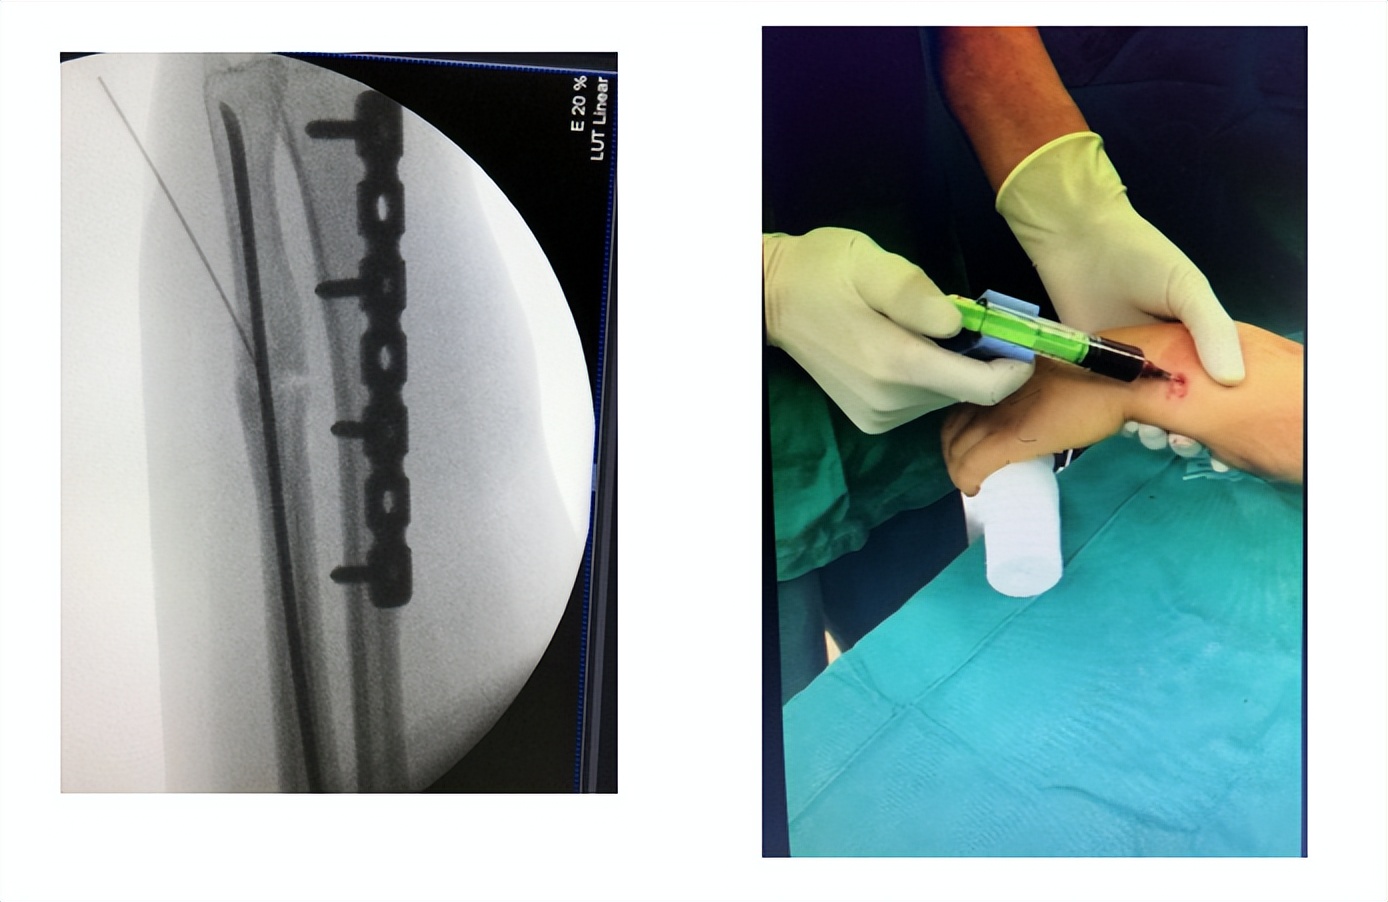

由于病人初次选择的是闭合复位的方式,创伤外科团队在仔细分析后,认为这个骨块仍然是有生物活性的。在和患者充分沟通后,在隋院长的主持下,创伤外科团队采用了生长因子注射的微创治疗方式。

(手术中定位,注射生长因子)

在C臂机的引导下定位骨不连区域,隋院长为患者注射生长因子,整个治疗过程不到5分钟时间,治疗结束后局部只有一个针眼。